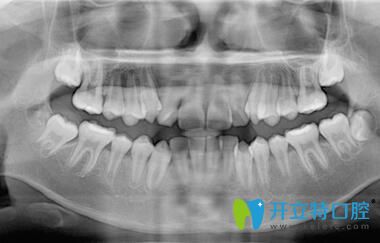

下面就來(lái)看下我矯正前的牙齒情況吧:

深圳正夫口腔的正畸醫(yī)生面診后,說(shuō)我的牙齒屬于牙列不齊、前牙擁擠;針對(duì)我的情況,又拍了牙片;然后才制定矯正方案,建議戴傳統(tǒng)金屬托槽或球面自鎖托槽,也把這兩種牙套的優(yōu)缺點(diǎn)和價(jià)格都做了詳細(xì)的介紹。